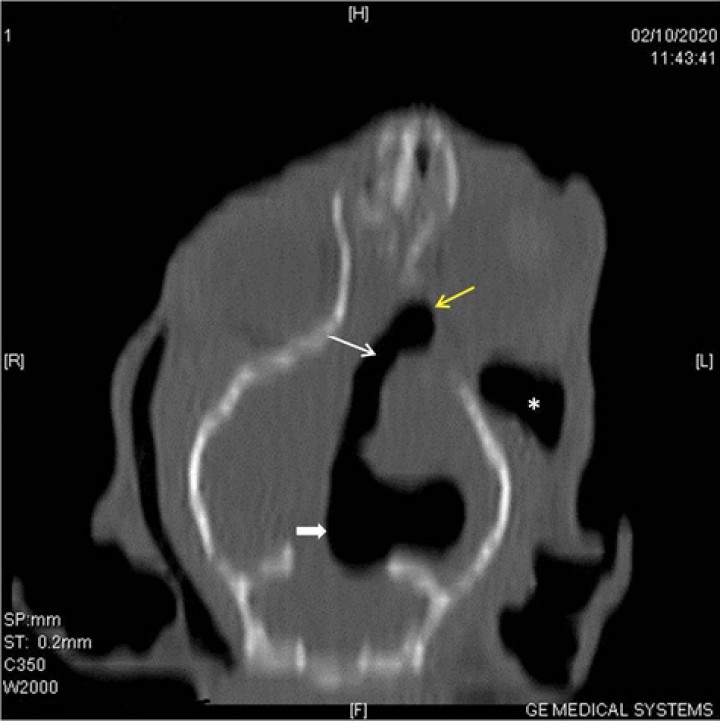

<p>TAC inicial. Cortes transversales en algoritmo de hueso del TAC, adquirido en algoritmo de tejido blando y hueso a 0,6 mm de grosor. (<strong>A</strong>) Corte caudal al seno frontal. Se observa una fractura simple y deprimida en la parte temporal del hueso frontal izquierdo (flecha blanca), desplazamiento de la fosa etmoidal en su unión con el hueso frontal del lado derecho (flecha amarilla), desplazamiento del meato etmoidal y preesfenoides (flecha negra), y fractura simple de la lámina perpendicular derecha del hueso palatino (flecha azul) (<strong>B</strong>) Corte a la altura de las bullas timpánicas que muestra una bóveda craneal íntegra y acúmulo moderado de aire en el tejido subcutáneo de la región temporal izquierda (flechas).</p>

TAC inicial. Cortes transversales en algoritmo de hueso del TAC, adquirido en algoritmo de tejido blando y hueso a 0,6 mm de grosor. (A) Corte caudal al seno frontal. Se observa una fractura simple y deprimida en la parte temporal del hueso frontal izquierdo (flecha blanca), desplazamiento de la fosa etmoidal en su unión con el hueso frontal del lado derecho (flecha amarilla), desplazamiento del meato etmoidal y preesfenoides (flecha negra), y fractura simple de la lámina perpendicular derecha del hueso palatino (flecha azul) (B) Corte a la altura de las bullas timpánicas que muestra una bóveda craneal íntegra y acúmulo moderado de aire en el tejido subcutáneo de la región temporal izquierda (flechas).

En la Fig. 1A se muestra una imagen transversal en algoritmo de hueso, caudal al seno frontal, en la que se observa una fractura simple y deprimida en la parte temporal del hueso frontal izquierdo, desplazamiento de la fosa etmoidal en su unión con el hueso frontal del lado derecho, desplazamiento del meato etmoidal y preesfenoides, y fractura simple de la lámina perpendicular derecha del hueso palatino. Además, también se puede constatar la presencia de una lesión hipoatenuante en comparación con el músculo, compatible con aire debajo de los músculos temporales, en mayor cantidad en el del lado izquierdo, en la zona retrobulbar dorso-medial, e intracraneal dorso-lateral izquierdo a modo de neumoencéfalo.

En el resto del estudio, además, se evidenciaron fracturas múltiples deprimidas en la parte orbital del hueso frontal bilateralmente a distintas alturas. También se observó una fractura simple y no desplazada en la lámina horizontal del hueso palatino del lado izquierdo, una fractura simple y deprimida en el maxilar derecho y una fractura no desplazada de la rama mandibular izquierda. Las zonas más caudales del cráneo resultaron sin fracturas (Fig. 1B).